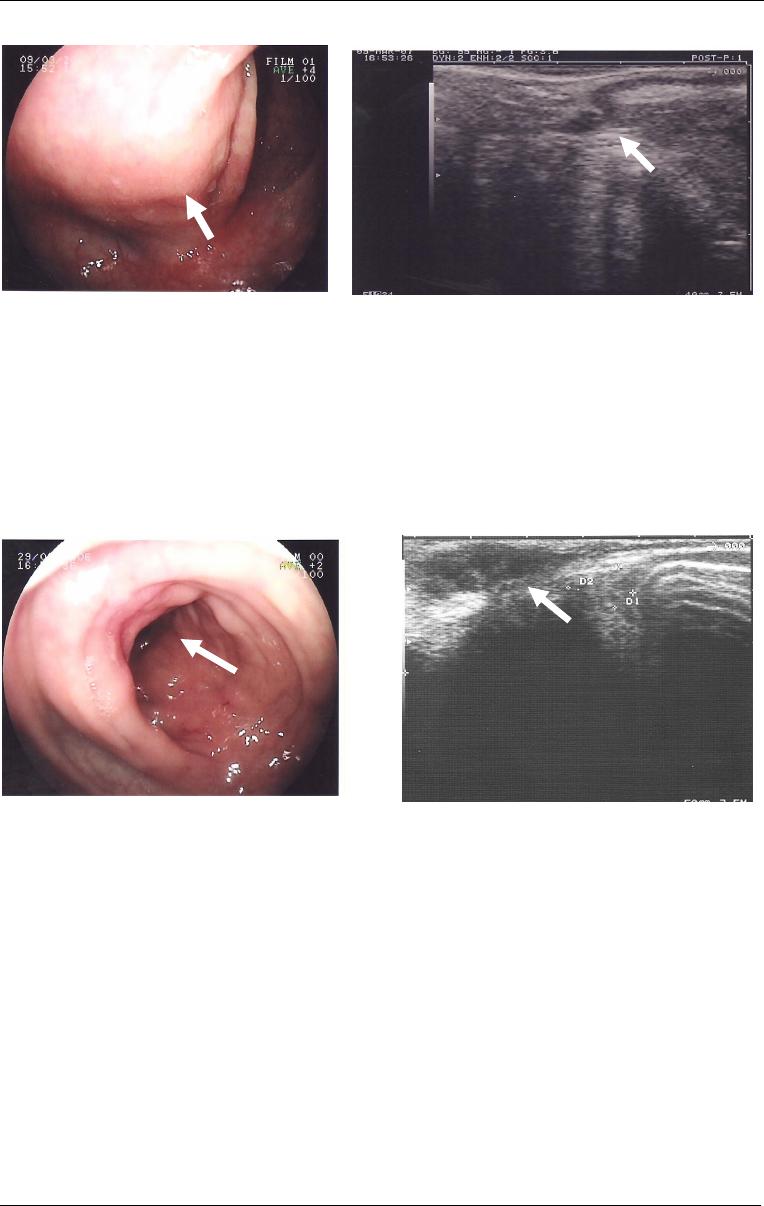

Figura

1

5

- Imagem de ecoendoscopia

(sete e meio megahertz) com punção

evidenciando espessamento da camada

muscular própria intestinal e a extremidade

distal da agulha de punção (seta). Obs:

imagem cedida por Dr. Lucio Rossini.

14

- Imagem de endossonografia

intestinal (sete e meio megahertz)

muscular própria de segmento intestinal

(seta) decorrente de endometriose

intestinal. Obs: imagem cedida por

Dr.Lucio Rossini.

A endossonografia intestinal é aplicada com sucesso no diagnóstico de lesões

submucosas do cólon, apresentando melhor especificidade quando associada à

punção para biópsia por aspiração guiada por ecoendoscopia (Giovannini et al, 1993;

Kameyama et al, 1997; Hara et al, 2003) ou a biópsias realizadas depois da secção

da camada mucosa com bisturi elétrico, respaldada pela prévia observação da

localização submucosa da lesão por ecoendoscopia (Catalano, 1994) (Figuras 14 e

15).